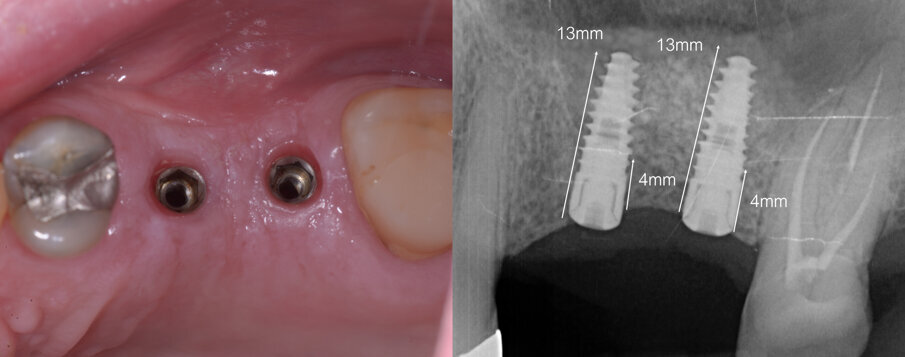

Si è proceduto di seguito all’innesto del sostituto osseo e al contestuale posizionamento implantare (Fig. 6). Dapprima si è posizionata, all’interno della cavità, una membrana in collagene (Biocollagen, Bioteck, Arcugnano) al fine di proteggere la membrana del seno durante le operazioni successive. La cavità è stata quindi parzialmente riempita utilizzando un sostituto osseo di origine equina in granuli spongiosi di dimensione 2-3 mm (Osteoxenon, Bioteck, Arcugnano). I granuli sono stati idratati con fisiologica sterile e miscelati con particolato autologo precedentemente prelevato dalla parete vestibolare utilizzando un bone scraper (Safescraper Twist, Meta, Reggio Emilia). Si è quindi proceduto al posizionamento di due impianti conici, entrambi di dimensione 4 x 13 mm (Avior, Mech & Human, Lissaro), utilizzando il protocollo di sottopreparazione descritto da Arosio e colleghi19. Il riempimento della cavità è stato completato utilizzando lo stesso sostituto in granuli e la finestra è stata protetta con una ulteriore membrana in collagene (Ossix-Plus, Datum Dental, Lod, Israele). I lembi sono stati suturati utilizzando una sutura non riassorbibile 5-0 (Polimid, Sweden & Martina, Due Carrare).

Fig. 6 - Dopo avere inserito una membrana a protezione della membrana sinusale, e dopo avere riempito parzialmente la cavità col sostituto osseo, si procede al posizionamento degli impianti. Il riempimento è completato e una seconda membrana viene posizionata a copertura della finestra di accesso. La sutura è eseguita con filamento in poliammide non riassorbibile.

Fig. 7 - Condizionamento dei tessuti molli ed endorale di controllo.